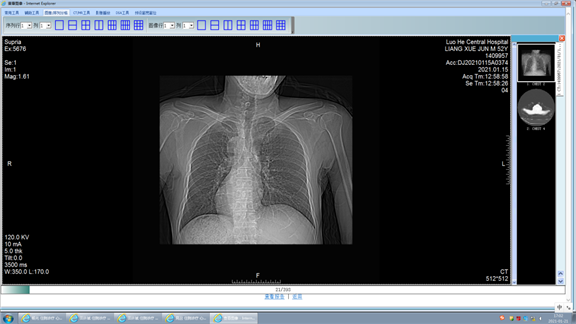

胸片显示右位心

来到漯河市中心医院入院后检查胸片和心脏彩超提示镜面右位心,且腹部超声发现内脏反转。漯河市中心医院心内二科电生理团队详细讨论,根据诊疗原则结合目前检查,决定为患者实施三维射频消融术根治室上速。